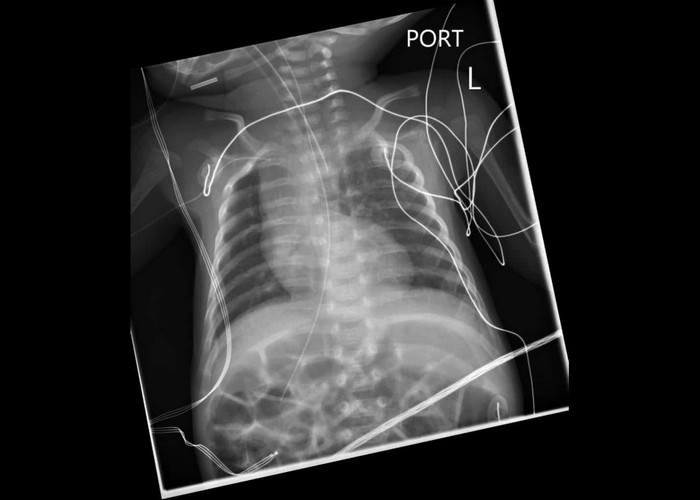

Dan Azire, ở Danbury, Connecticut (Mỹ), mắc chứng exostoses di truyền khiến anh có thêm khoảng 92 chiếc xương (người thường chỉ có 206 xương). Anh ta đã phải phẫu thuật nhiều lần mới loại bỏ được 42 xương thừa.